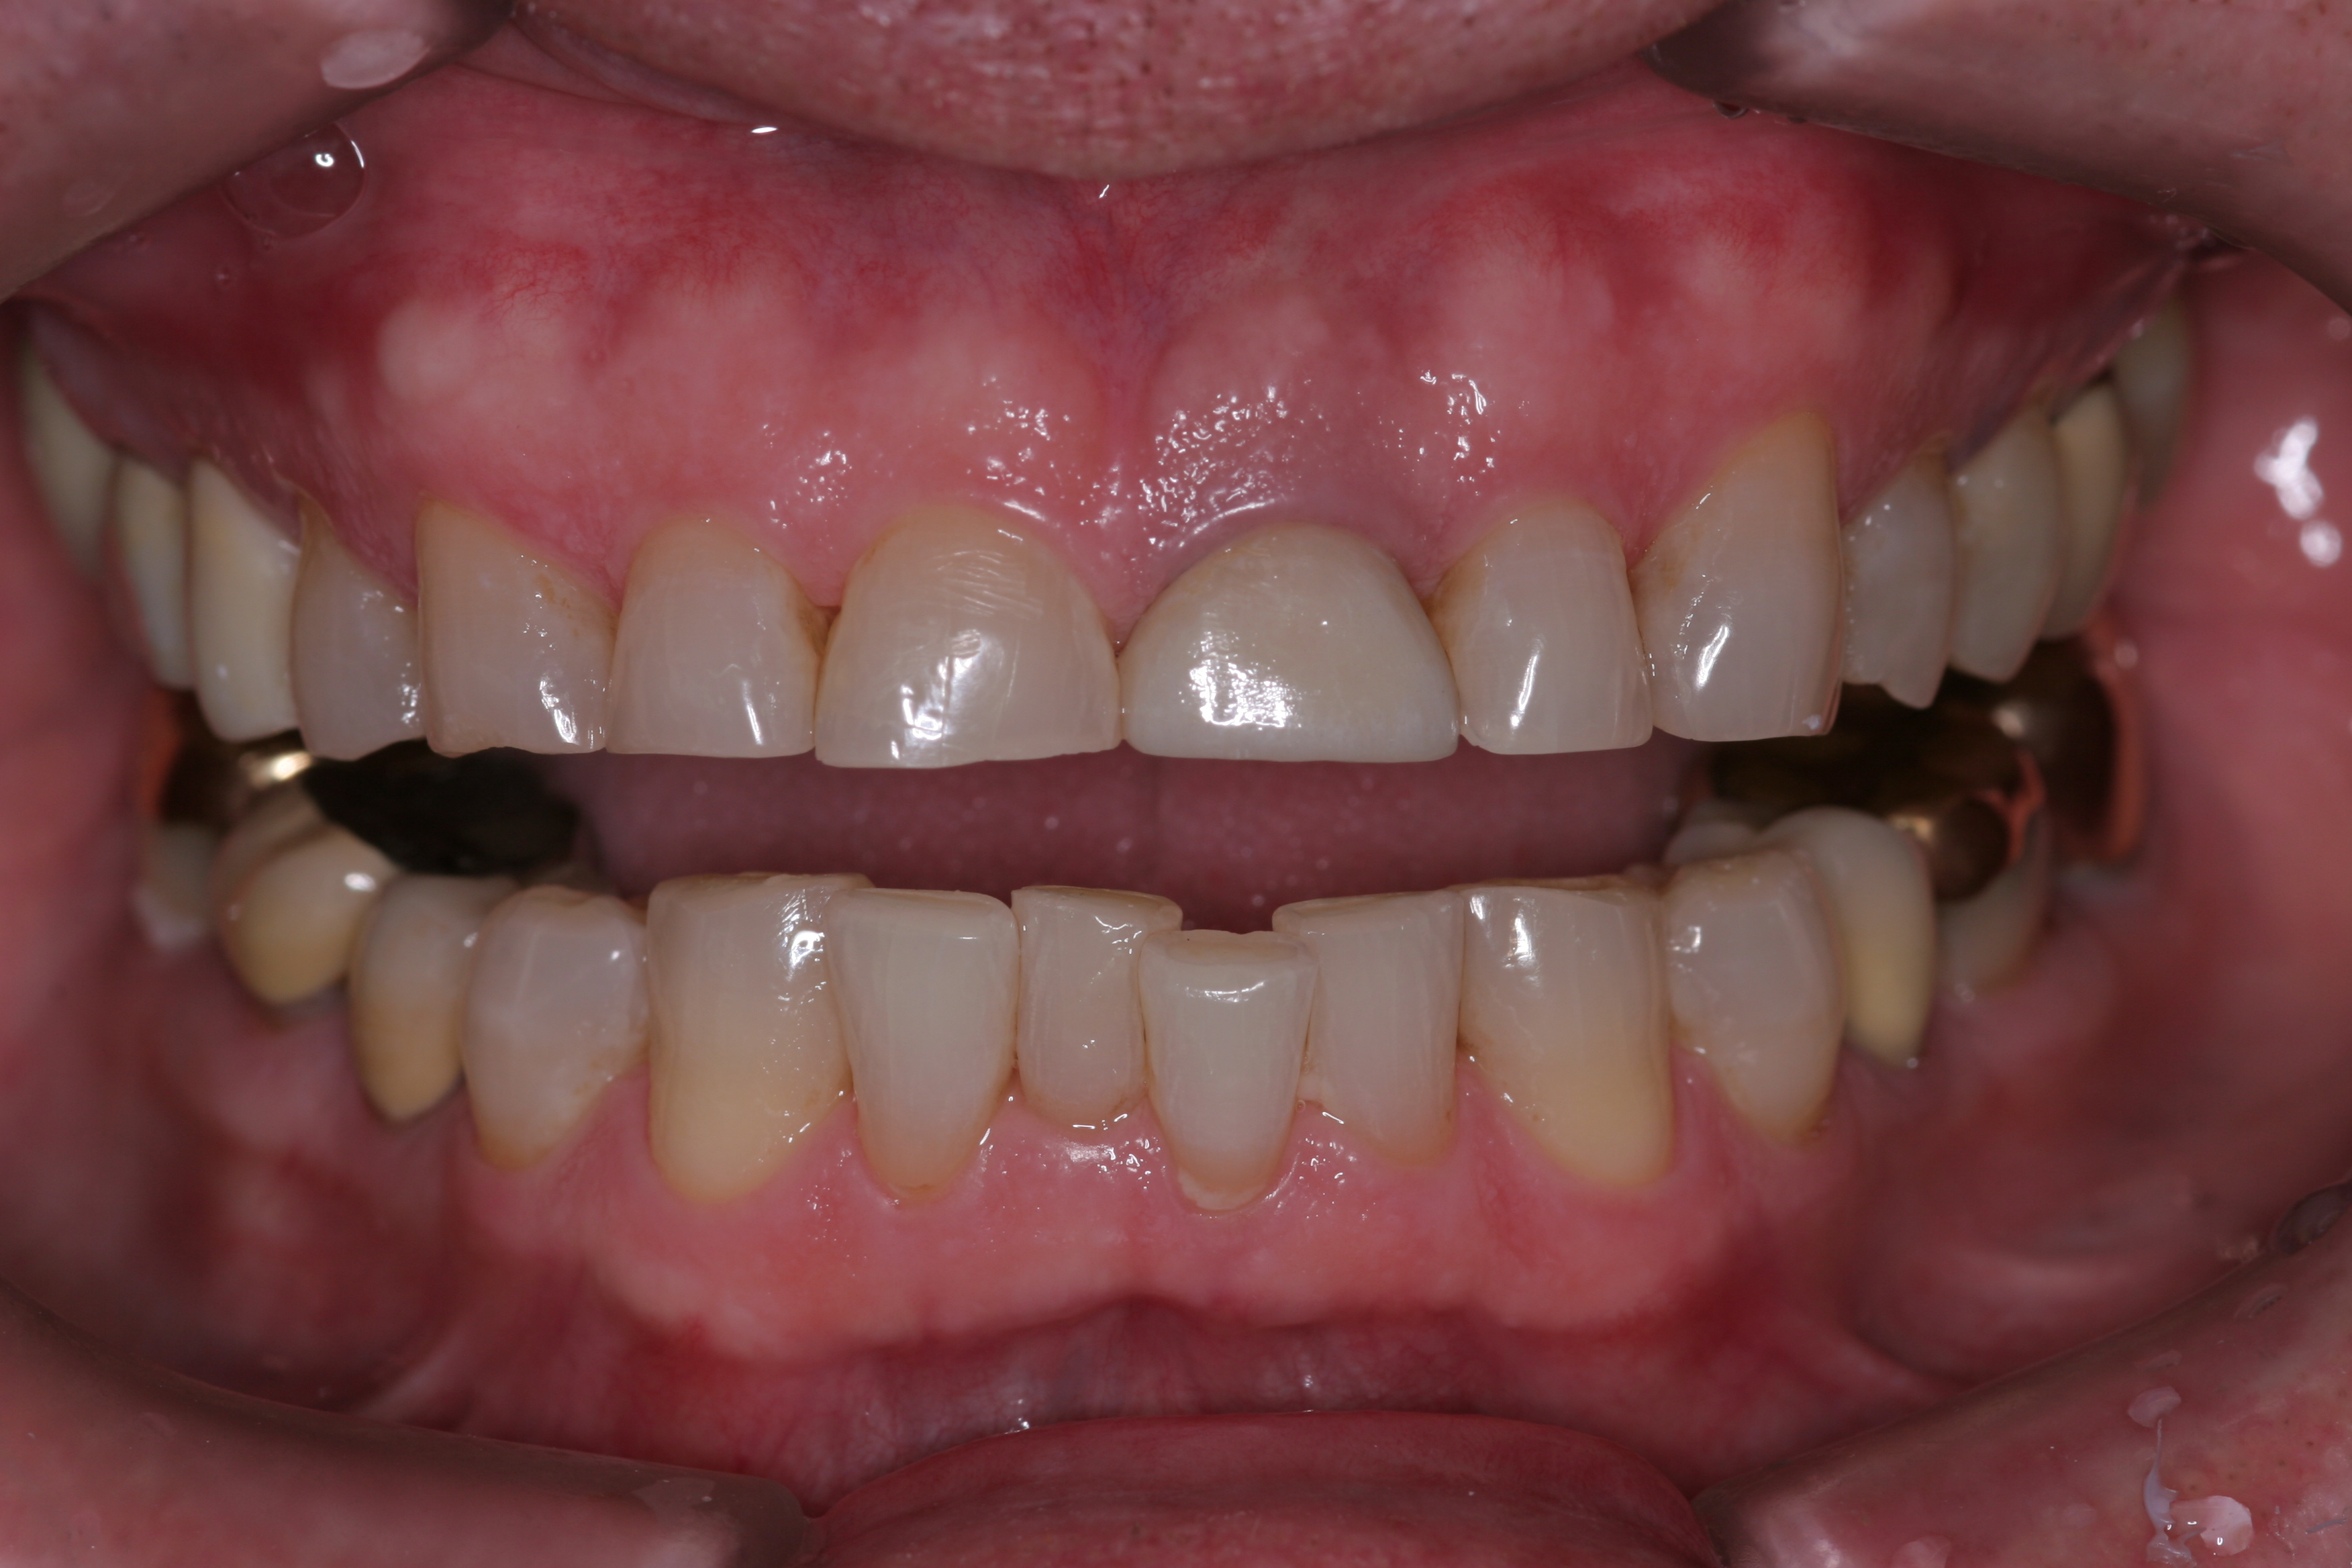

A patient presented with advanced generalized wear of her anterior teeth (Figure 10 and Figure 11). She was displeased with their overall appearance because of their color and wear (Figure 12). A complete examination was performed, revealing instability in her temporomandibular lateral poles bilaterally, sore muscles of mastication, advanced wear, a CR/MIP discrepancy, and loss of her anterior guidance due to the wear. Although the topic is beyond the scope of this article, the patient was also screened for possible sleep apnea. This included an evaluation of the Mallampati score, previous sleep therapy evaluation or treatment, snoring history, an evaluation of her neck size, her weight status, and the presence of the tonsils and their size. In every case, if this clinician suspects airway obstruction to be playing a role in tooth wear issues, the patient is referred to a sleep physician. The patient in this case displayed few apnea risk factors, and the patient’s anterior wear facets fit together like a “lock and key” pattern seen in parafunctional activity. Splint therapy was initiated to stabilize the joints and muscles. A repeatable CR position was verified through load testing. At this point diagnostic models, photographs, a CR bite record, and a facebow were taken and recorded.

(10.) A patient presented with advanced generalized wear of her anterior teeth, and was displeased with their overall appearance because of their color and wear.

Figure 10

(11.) A patient presented with advanced generalized wear of her anterior teeth, and was displeased with their overall appearance because of their color and wear.

Figure 11

(12.) A patient presented with advanced generalized wear of her anterior teeth, and was displeased with their overall appearance because of their color and wear.

Figure 12